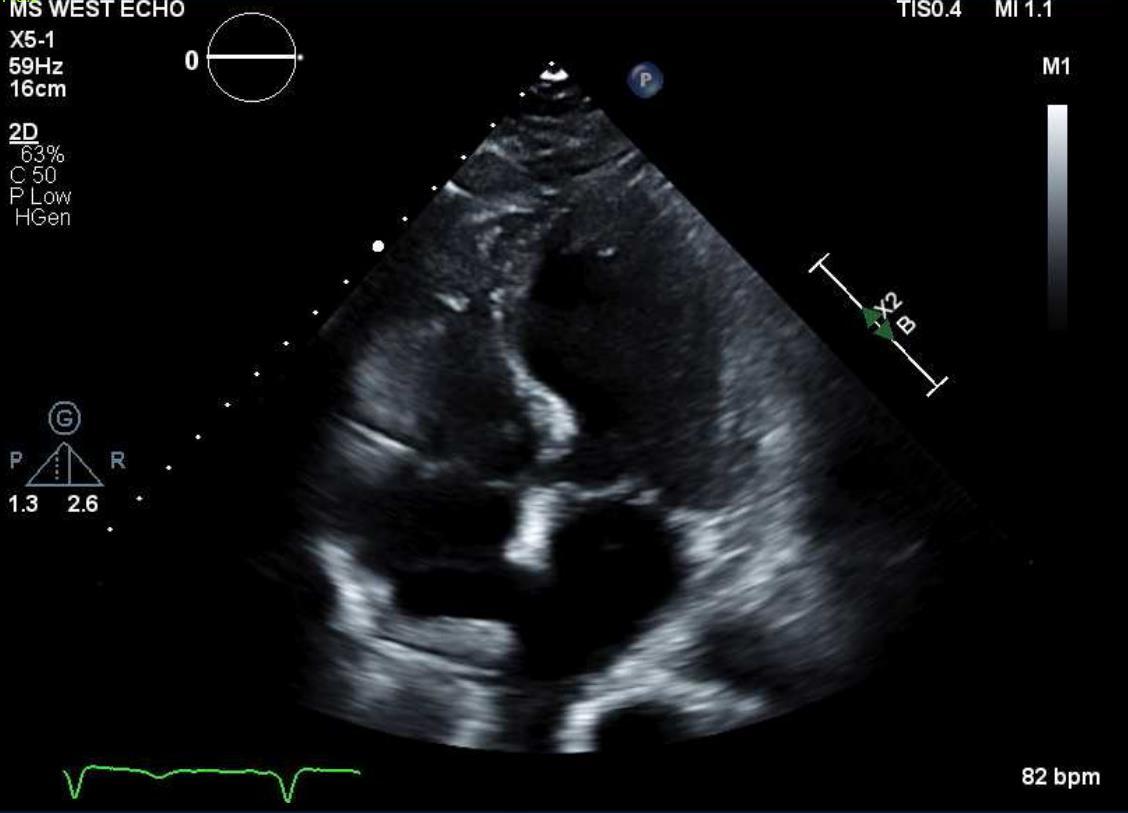

CARDIAC SARCOIDOSIS WITH PREDOMINANT RIGHT VENTRICLE INVOLVEMENT

Hannah Hart1, Devika Aggarwal1, Soumya Gupta1, Vikram Agarwal1, Isha Ranadive1

1Mount Sinai Morningside-West Hospitals, Icahn School of Medicine at Mount Sinai, New York, NY, United States

Presented at both the American College of Cardiology (ACC) Annual Meeting that was held in Atlanta, Georgia, United States from April 6-8, 2024 and the Annual Mount Sinai Health System Department of Medicine Research Day that was held in New York, New York, United States on May 6-7, 2024.